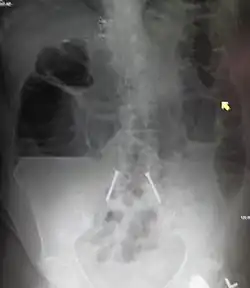

Radiological signs of bowel obstruction include bowel distension (small bowel loops dilated >3 cm) and the presence of multiple (more than 2) air-fluid levels on supine and erect abdominal radiographs.[16] Ultrasounds may be as useful as CT scanning to make the diagnosis.[17]

Small bowel obstruction on ultrasound[19]

-